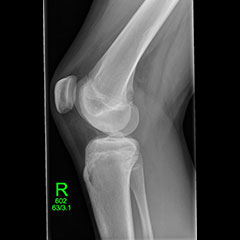

Knee pain

Knee pain is common in physically active adolescents, who can sometimes experience pain in the front and centre of the knee, usually underneath the kneecap (patella). Adolescent anterior knee pain is not usually caused by an abnormality within the knee, but by overuse or a training routine that does not include adequate stretching or strengthening exercises. In most cases, simple measures like rest, over-the-counter medication and strengthening exercises relieve anterior knee pain and allow the young athlete to return to his or her favourite sports.

Adolescent knee pain